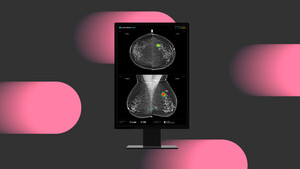

루닛은 의료진과 AI간 상호작용에 관한 연구 결과가 북미영상의학회(RSNA)가 발행하는 세계적인 영상의학 학술지 'Radiology(IF 12.1)'에 게재됐다고 9일 밝혔다.스웨덴 최대 규모 사립병원 '카피오 세인트괴란 병원 카린 뎀브로워 박사 연구팀이 주도한 이번 연구는 지난 2023년 9월 '란셋 디지털 헬스'에 게재된 전향적 연구 'ScreenTrustCAD'의 후속 분석으로 진행됐다.연구팀은 2021년 4월부터 2022년 6월까지 유방암 검진을 받은 여성 약 5만5000명의 데이터를 활용해 영상의학과 전문의와 유방촬영술 A...